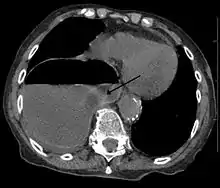

| Diagram of the formation of a ring chromosome | |